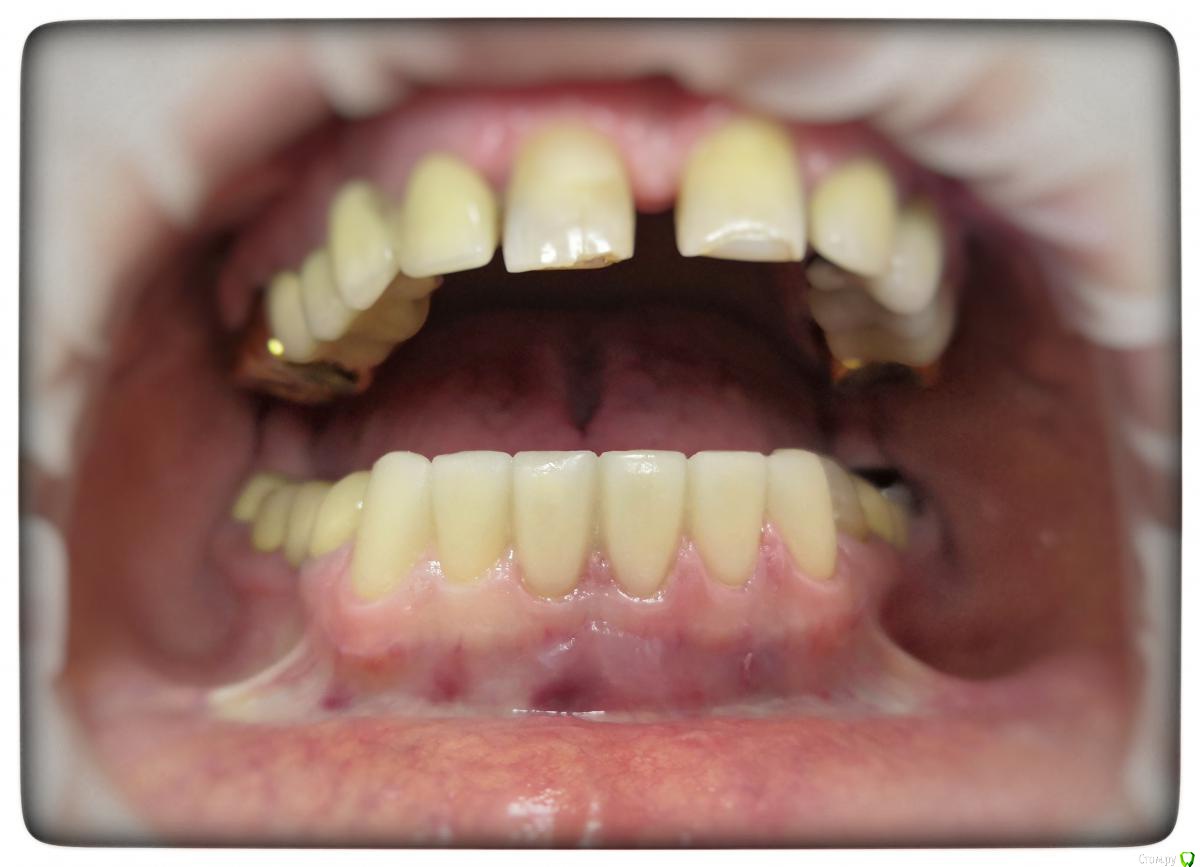

Sagaydak Aleksandr Опубликовано 18 апреля, 2019 Автор Поделиться Опубликовано 18 апреля, 2019 Зафиксировал виниры. Прошло 1,5 недели. Пациент отмечает продолжение чувствительны от температурный раздражителей. Фиксировал под анестезией, три часа. Под конец фиксации пациент отмечал очень сильную чувствительность, через два дня отметил небольшое облегчение. По ночам все спокойно. Назначил пасты для снижения чувствительности. Два раза обработал зубы десенсетином. Подскажите, дальше наблюдать или может все вообще переделать? Ссылка на комментарий

Sagaydak Aleksandr Опубликовано 18 апреля, 2019 Автор Поделиться Опубликовано 18 апреля, 2019 Сегодня был осмотр. При зондировании чувствительная зона пришейки ниже границы прилегания. По прилеганию все хорошо, все сидит на своих местах. Попробую сделать каппу как посоветовали. Ссылка на комментарий